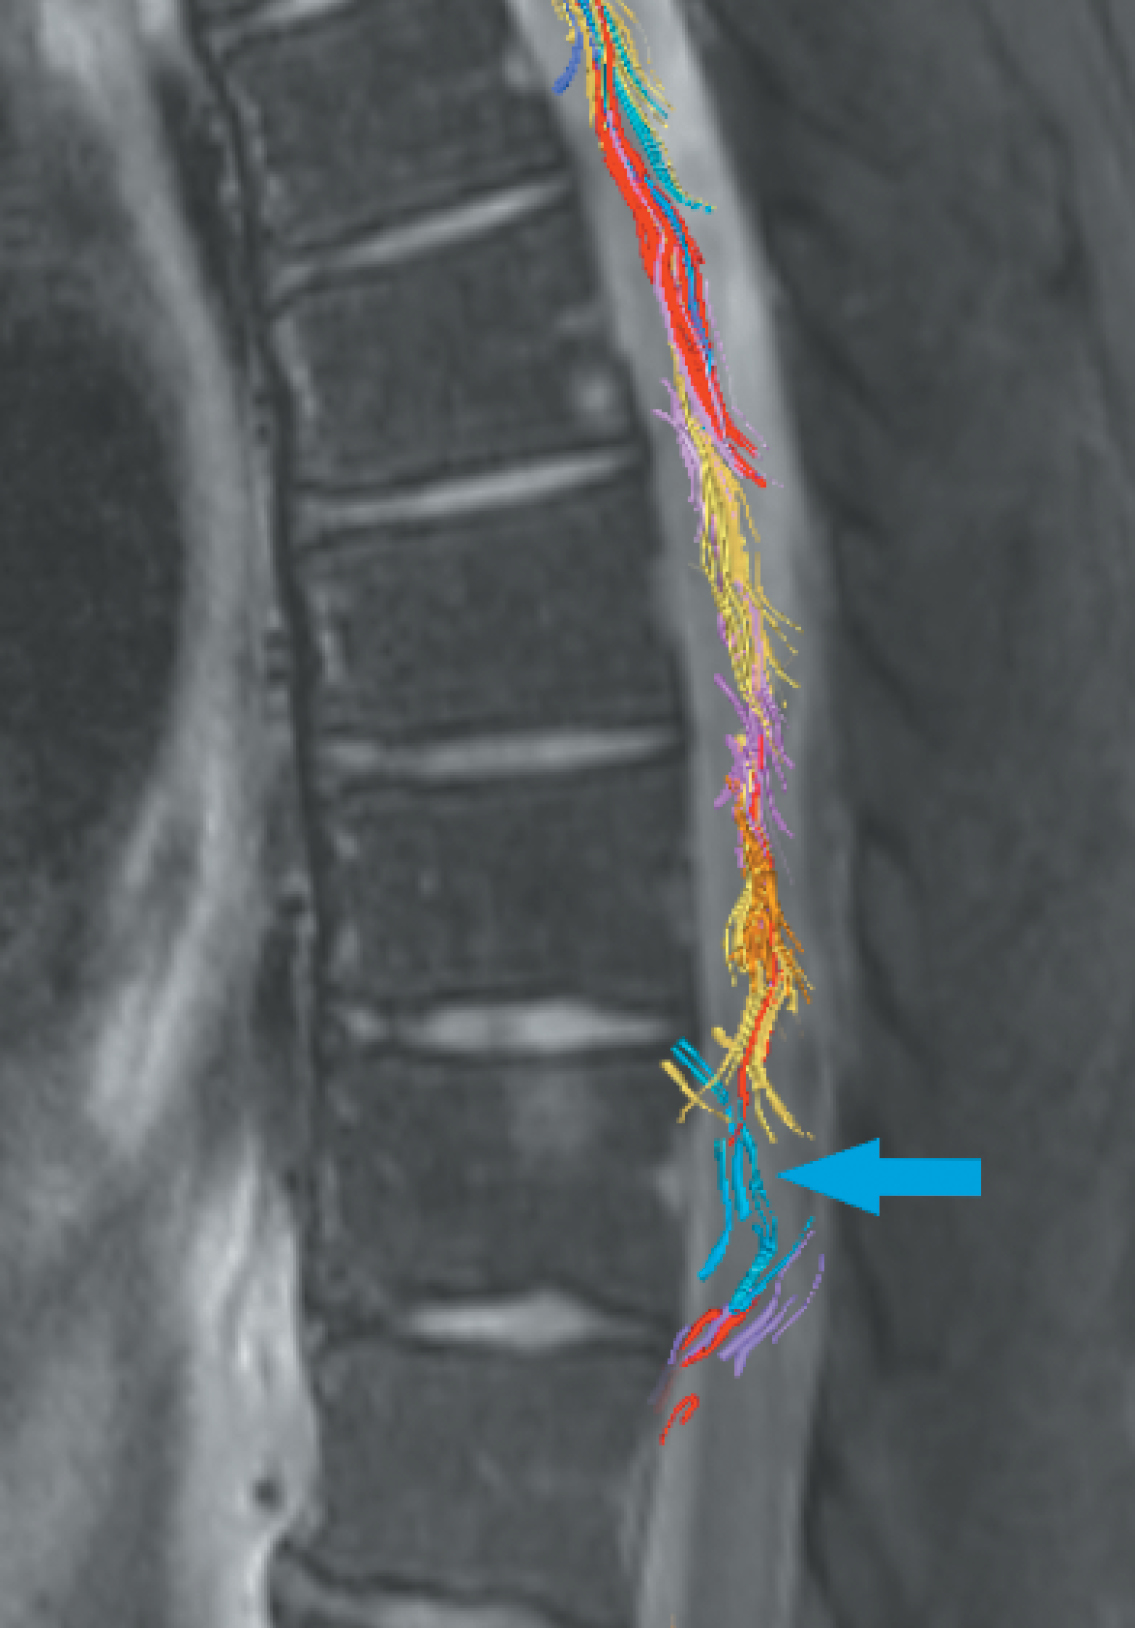

В проведённых исследованиях отмечается важная диаг-ностическая роль ДТИ благодаря его способности оценивать микроструктурную целостность белого вещества путём измерения количественных диффузионных метрик: площади поперечного сечения как меру атрофии СМ, фракционной анизотропии для оценки целостности аксонов, коэффициента переноса намагниченности как показателя демиелинизации и среднюю диффузию в очаге ишемии и перифокальных зонах [49]. При напряжённости поля ≥ 3 Тл Т2-ВИ обеспечивает высокое разрешение и сильный контраст между серым и белым веществом, позволяя сегментировать эти структуры и вычислять площадь их поперечного сечения (рис. 5) [50].

Рис. 5. Диффузионно-тензорное МР-исследование с 3D-тракто-граммой с цветовым кодированием пациента В. с венозной недостаточностью СМ на уровне Th9–Th11.

Голубым цветом выделены проводящие волокна на уровне Th9–Th11, демонстрируется нарушение пространственной ориентации волокон в очаге ишемии (голубая стрелка), фракционная анизотропия 0,46 ± 0,18, измеряемый коэффициент диффузии 0,79 ± 0,15 × 103 мм2/с.

Fig. 5. 3D DTI color-coded tractography map of patient V. with spinal venous insufficiency at Th9–Th11.

Conducting fibers at Th9–Th11 are highlighted in blue, demonstrating abnormal spatial orientation of the fibers in the ischemic lesion (blue arrow), fractional anisotropy 0.46 ± 0.18, apparent diffusion coefficient 0.79 ± 0.15 × 103 mm2/sec.